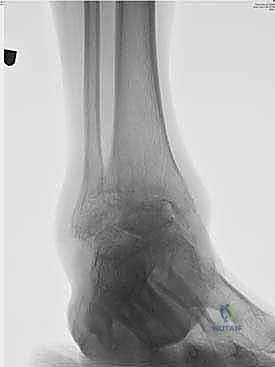

عملية تثبيت مفصل الكاحل والقدم الخلفية، والمعروفة طبياً بـ (Tibiotalocalcaneal Arthrodesis)، هي إجراء جراحي معقد يهدف إلى دمج (لحام) ثلاثة عظام رئيسية معاً لتكوين كتلة عظمية واحدة صلبة وغير متحركة. هذه العظام هي: عظمة الساق الكبرى (Tibia)، وعظمة الكاحل (Talus)، وعظمة الكعب (Calcaneus).

يتم هذا الدمج باستخدام مسمار نخاعي (Intramedullary Nail) طويل وقوي يُدخل من أسفل الكعب ليخترق العظام الثلاثة، ويتم تثبيته ببراغي قفلية لضمان أقصى درجات الثبات. الهدف من إلغاء الحركة في هذه المفاصل التالفة هو القضاء التام على الاحتكاك العظمي الذي يسبب الألم المبرح، مما يوفر للمريض قاعدة ثابتة وقوية للمشي.

يعتمد الدكتور هطيف على الأشعة السينية (X-rays) والأشعة المقطعية (CT Scans) ثلاثية الأبعاد لبناء خريطة دقيقة للتشوهات العظمية وتحديد حجم ومسار المسمار النخاعي المناسب لكل مريض بدقة متناهية. يتم مناقشة كل هذه التفاصيل بشفافية تامة مع المريض.